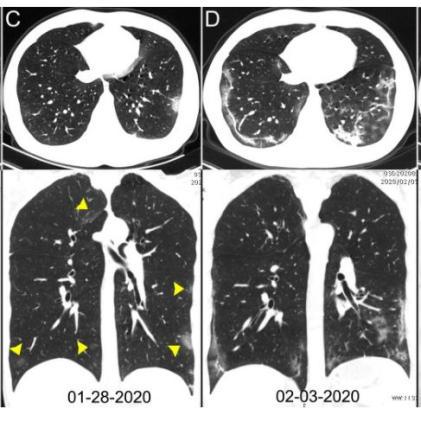

早期出现小斑片或间质性改变,常有磨玻璃阴影;

病灶主要位于胸膜下。随着病情进展,病灶常为双肺多发。

随着病情进展,CT失去特异性,不容易鉴别与一般的肺炎。

特别是后期变成“白肺”,没有之前的影像学做对比,更是没办法做出准确的诊断。